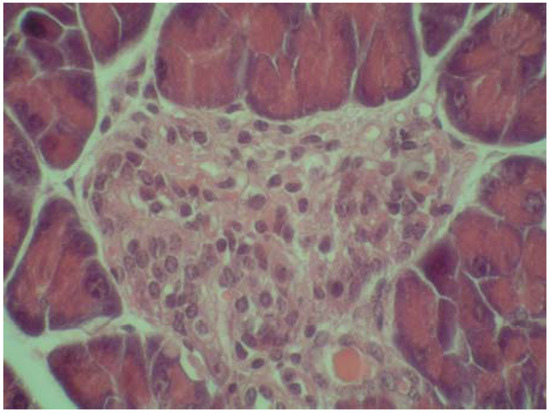

2.4. Cytoprotective effect against alloxan-induced diabetes

3.7. Cytoprotective effect against alloxan-induced diabetes